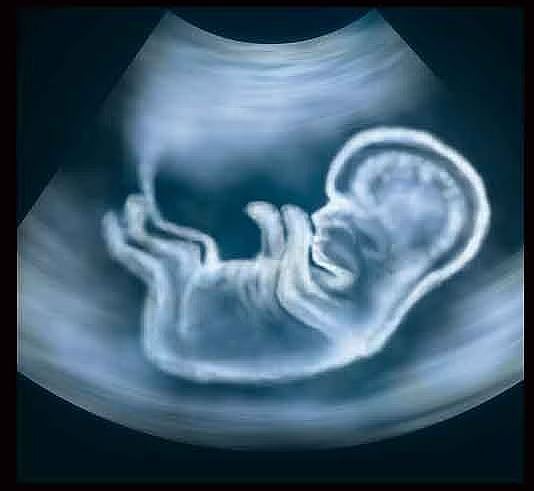

पुणे : पुढारी वृत्तसेवा : बेकायदेशीर गर्भलिंग निदानाचे गैरप्रकार रोखण्यासाठी सार्वजनिक आरोग्य विभागातर्फे कडक कारवाई केली जाते. आरोग्य विभागातर्फे १ एप्रिल २०२३ ते ३० मार्च २०२४ या कालावधीत राज्यात ७९ ठिकाणी स्टिंग ऑपरेशन करण्यात आली. यामध्ये ७ ठिकाणी कारवाई करण्यात यश मिळाले. कोल्हापूरमध्ये ३, छत्रपती संभाजीनगरमध्ये २, धाराशिवमध्ये १ आणि बीडमध्ये १ अशा केंद्रांवर कारवाई करण्यात आली आहे.

प्रसूतीपूर्व निदान तंत्राचा वापर करून बेकायदेशीररीत्या गर्भलिंग निदान करणे, गर्भपात करणे शिक्षेस पात्र आहे. मुलीचे प्रमाण मुलांच्या तुलनेत कमी होत असताना या सामाजिक समस्येकडे सर्वांनी गांभीयनि लक्ष देण्याचे आवाहन शासनातर्फे करण्यात आले आहे. नुकतेच छ. संभाजीनगर येथील बेकायदेशीर गर्भलिंग निदानाचे प्रकरण समोर आले. या पार्श्वभूमीवर तेथील जिल्हाधिकाऱ्यांना सतर्कतेचा इशारा देण्यात आला आहे.

सोनोग्राफी केंद्रात गर्भधारणापूर्व व प्रसूतीपूर्व निदान तंत्रे (लिंग निवडीस प्रतिबंध) कायदा १९९४ चे उल्लंघन होत असल्याचे आढळून आल्यास, तसेच असे कृत्य करण्याची जाहिरात करणा-यांची तक्रार आरोग्य विभागाच्या टोल फी. क्र. १८०० २३३ ४४७५ किंवा १०४ या क्रमांकावर नागरिकांनी नोंदवावी. या बाबीची खातरजमा करून संबंधित सोनोग्राफी केंद्रावर, व्यक्तीवर न्यायालयीन प्रकरण दाखल केले जाते, अशी माहिती अतिरिक्त संचालक डॉ. रेखा गायकवाड यांनी दिली